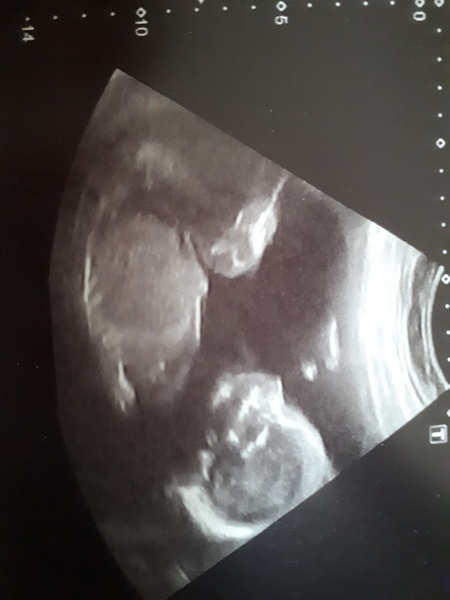

So the scan went really well, all growing as it should be and (as I thought) we're on Team Pink. Matilda was very co-operative with the scan, was waving away and moving her legs and apparently has her feet right up under my ribs already. Placenta is anterior but nice and high and my cervical length is good (I had a LLETZ procedure years ago so may need a suture but it's all good at the moment).

Yayyyyyyy team pink 💖💖💖

She's got the cutest little nose on her scan xx